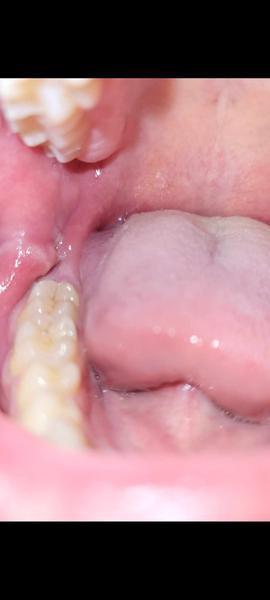

Čo spôsobuje opuch na líci vľavo?

@lilyianka Ked si to z prstom trošku pohnem tak vnutri to je ako keby otvorene na 2 polovice , neviem to lepšie vysvetlit ..... celkom sa bojim

Mas poskodenu sliznicu a dostali sa ti tam bakterie z ust, tak sa ti to zapalilo. Nieco ako afta.

Mne to príde ako keď si zakusneš zubami do líca.